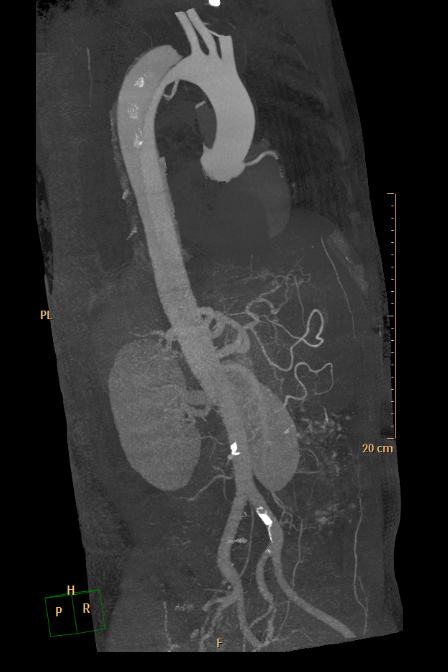

▲ 实例:主动脉瘤合并夹层腔内治疗+弓上三分支腔内重建(血管外科王兵教授团队)